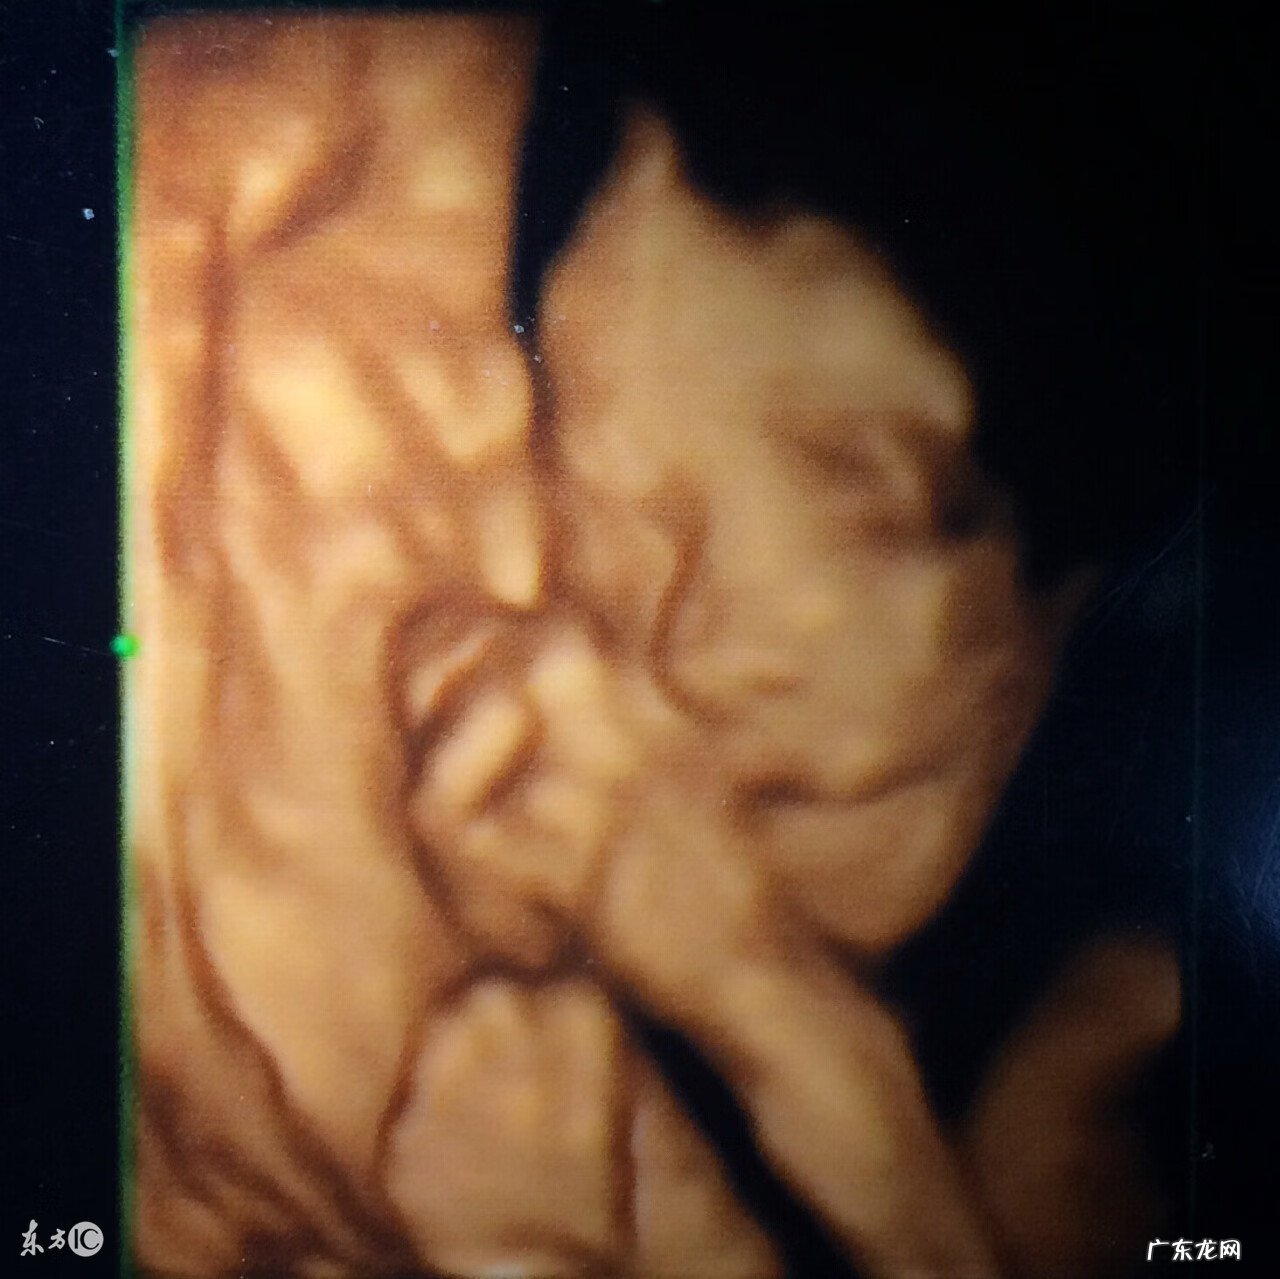

四维彩超怎么分辨男女?四维彩超是孕期确认胎儿性别最直观最简单的方法,而且准确率也很高 。那么,四维彩超怎么分辨男女?四维彩超怎么看性别呢?

四维彩超怎么分辨男女四维彩超可以通过直接看胎儿生殖器官分辨出胎儿性别 。

四维彩超跟其他超声检查相比,可以实时观察人体内部器官的动态运动,当然也能准确地看出胎儿生殖器官是什么样,从而判定胎儿的性别 。在怀孕12周之后开始胎儿生殖器官的发育就开始有差异性了,一般女宝宝的小芽会分开往里面发育,而男宝宝的则开始变成像外突出发育为小JJ,这些在15周之后通过四维彩超都能清晰的看出来 。